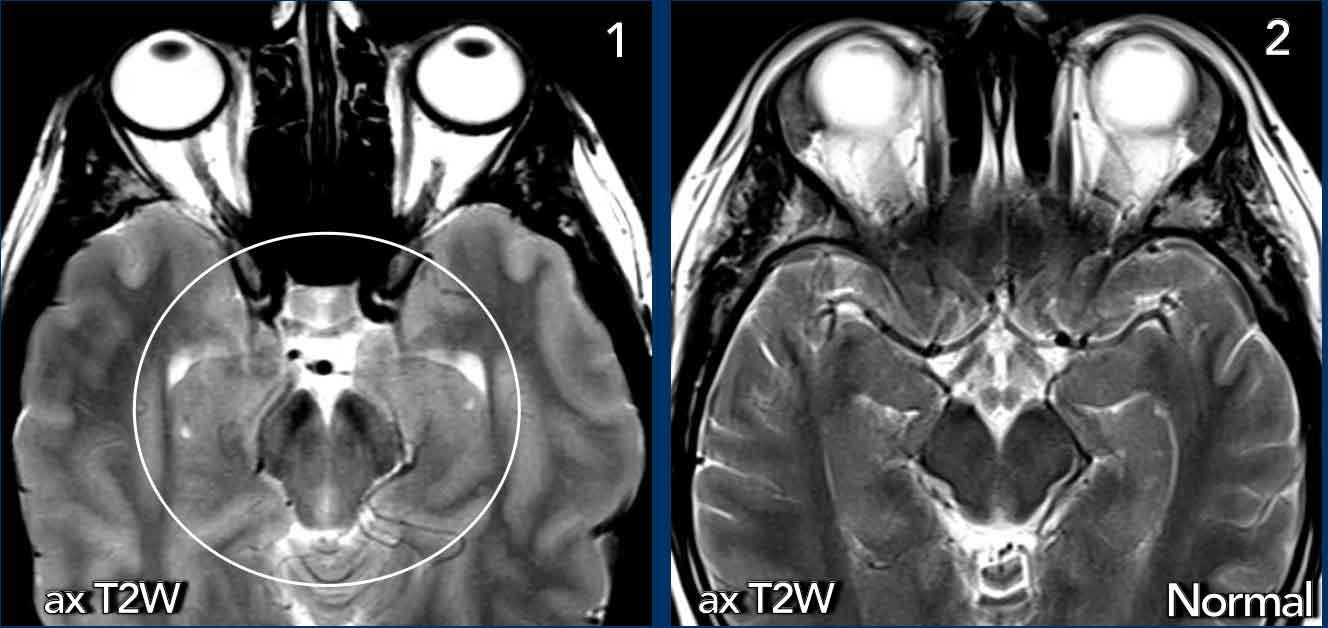

Trên các lát cắt axial, sự dịch chuyển xuống dưới của não dẫn đến chèn ép trung não.

Hình ảnh

- Hình ảnh võng xuống với trung não bị chèn ép từ hai phía (vòng tròn).

- Trung não bình thường để so sánh.